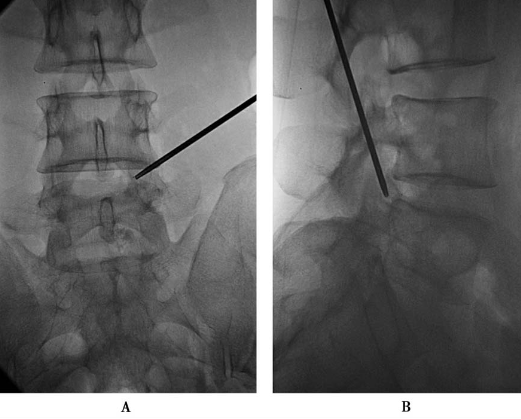

上关节突尖的腹侧(图12):调整勺状针的勺状面向腹侧,稍加大穿刺角度,使针尖略向腹侧进针,滑过上关节突尖部进入椎间孔,注入局麻药3ml。

图12勺状针针尖抵达上关节突尖的腹侧A.前后位透视;B.侧位透视